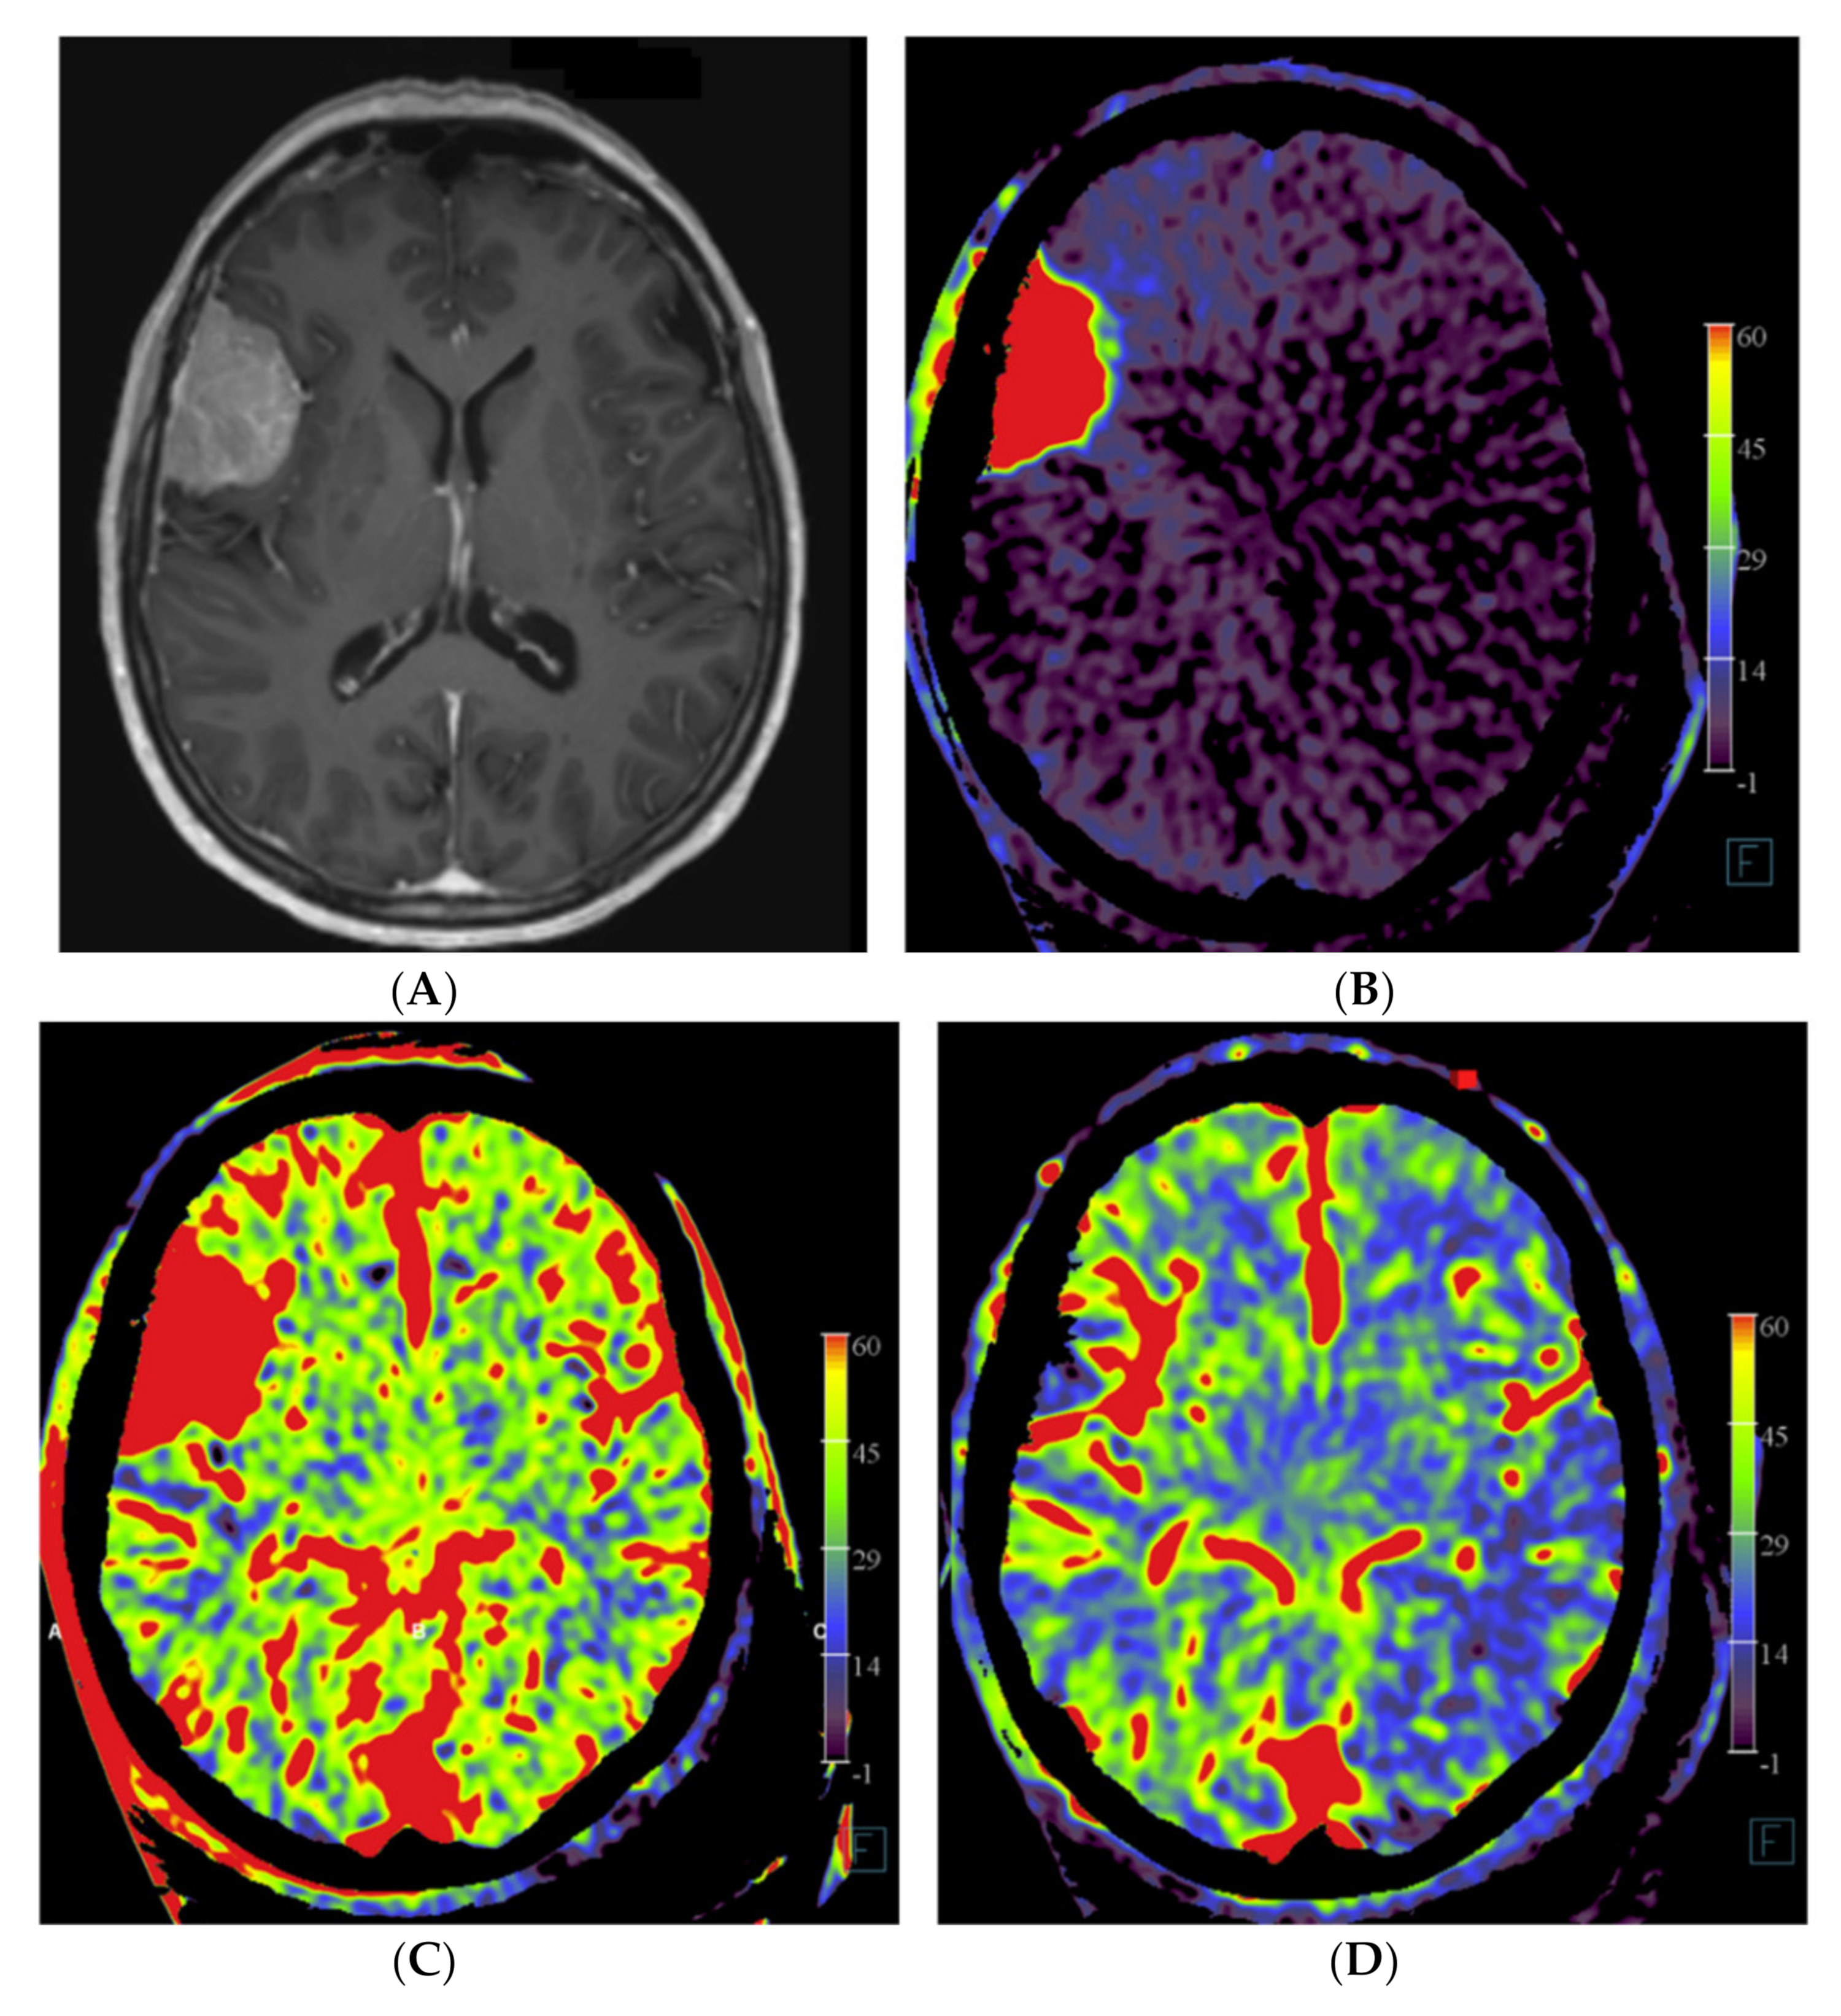

In patient no. 3, with a transitional meningioma located at the left sphenoid ridge, a predominant pial vascular supply was present. No embolization was done because it was considered not helpful for the resection (Figure 3).

Figure 3.

Patient no. 3 presented with a very large sphenoid ridge meningioma on the left side. (A) Axial 3 mm reformation based on fill run images shows the large tumor with encasement of the distal internal carotid artery (arrow) and the middle cerebral artery on the left. (B) Coronal reformation of whole brain PBV perfusion imaging compared to (C) coronal reformation of selective PBV perfusion by injection of the left external carotid artery shows predominant pial blood supply and only limited dural supply to the tumor. In this case, pre-operative embolization was not pursued because it was considered not helpful for reducing the surgery risk in comparison to the risk of the embolization procedure.

The operation time varied between 3 h and 40 min (patient no. 5) to 14 h (patient no. 3) of surgery. The longest operation time correlated with the patient with the predominant pial arterial supply (patient no. 3, Figure 3), in which an external to internal bypass (from superficial temporal artery to middle cerebral artery) was constructed. Negligible blood loss (<50 mL) was present in patients no. 2, 4 and 5. In patients no. 1 and 3, a blood loss of 500 mL and 300 mL was observed, respectively. The post-operative course was uneventful for all patients.